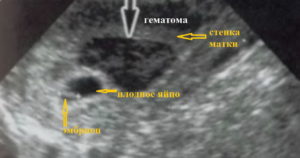

Вместе с отслоением хориона начинают разрываться сосуды, за счет которых он внедрился в матку, в этой области образуется гематома. Именно это и будет самым первым симптомом отслоения, которое обнаруживается на ультразвуковой диагностике. В случае частичной или не сильно выраженной отслойки, гематома может быть единственным проявлением данного патологического состояния.

Очень важно отметить, что любая женщина, даже абсолютно здоровая, может столкнуться с угрозой прерывания беременности. Плодное яйцо начинает отделяться от оболочки, хориона и это является началом выкидыша. В месте отслойки появляется ретрохориальная гематома. Постепенно она начинает расти и происходит полное отслоение плодного яйца, что называется самопроизвольным абортом.

УЗИ-исследование – это основной способ диагностики этой патологии наряду с общим осмотром врача гинеколога. С помощью ультразвука доктор сможет увидеть наружную оболочку плодного яйца и оценить, в каком она состоянии. Также для него будет важным наличие гематомы между плодным яйцом и хорионом, то есть его оболочкой.

Состояние плода также необходимо оценить. С шестой недели возможно прослушать его сердцебиение. А само плодное яйцо на УЗИ можно обнаружить уже к концу первого месяца беременности.

Плодное яйцо начинает отторгаться от хориона, здесь образуется ранка вследствие повреждения сосудов, за плодной оболочкой скапливается кровь, образуя гематому, из-за чего это явление в акушерстве называется еще ретрохориальной гематомой.

Отслойка плодного яйца – это начало самопроизвольного аборта (выкидыша). Яйцо начинает отделяться от плаценты, повреждая тем самым сосуды. В месте разрыва образуется гематома. Она начинает увеличиваться, вызывая дальнейшее отслоение.

Диагностировать данную патологию можно только при помощи УЗИ, на котором будет видно повреждение. По размерам гематомы можно определить степень риска для женщины и ребёнка и назначить соответствующее лечение в стационаре.